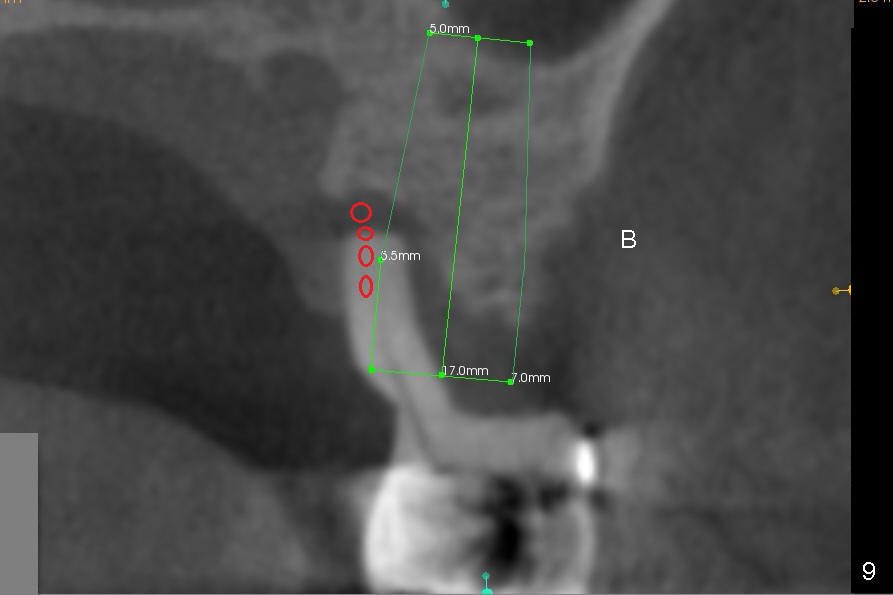

The tooth #14 is periodontally compromised with supraeruption (Fig.8-10). After immediate implant, bone graft (red circles) is needed distally (Fig.8) and palatally (Fig.9).